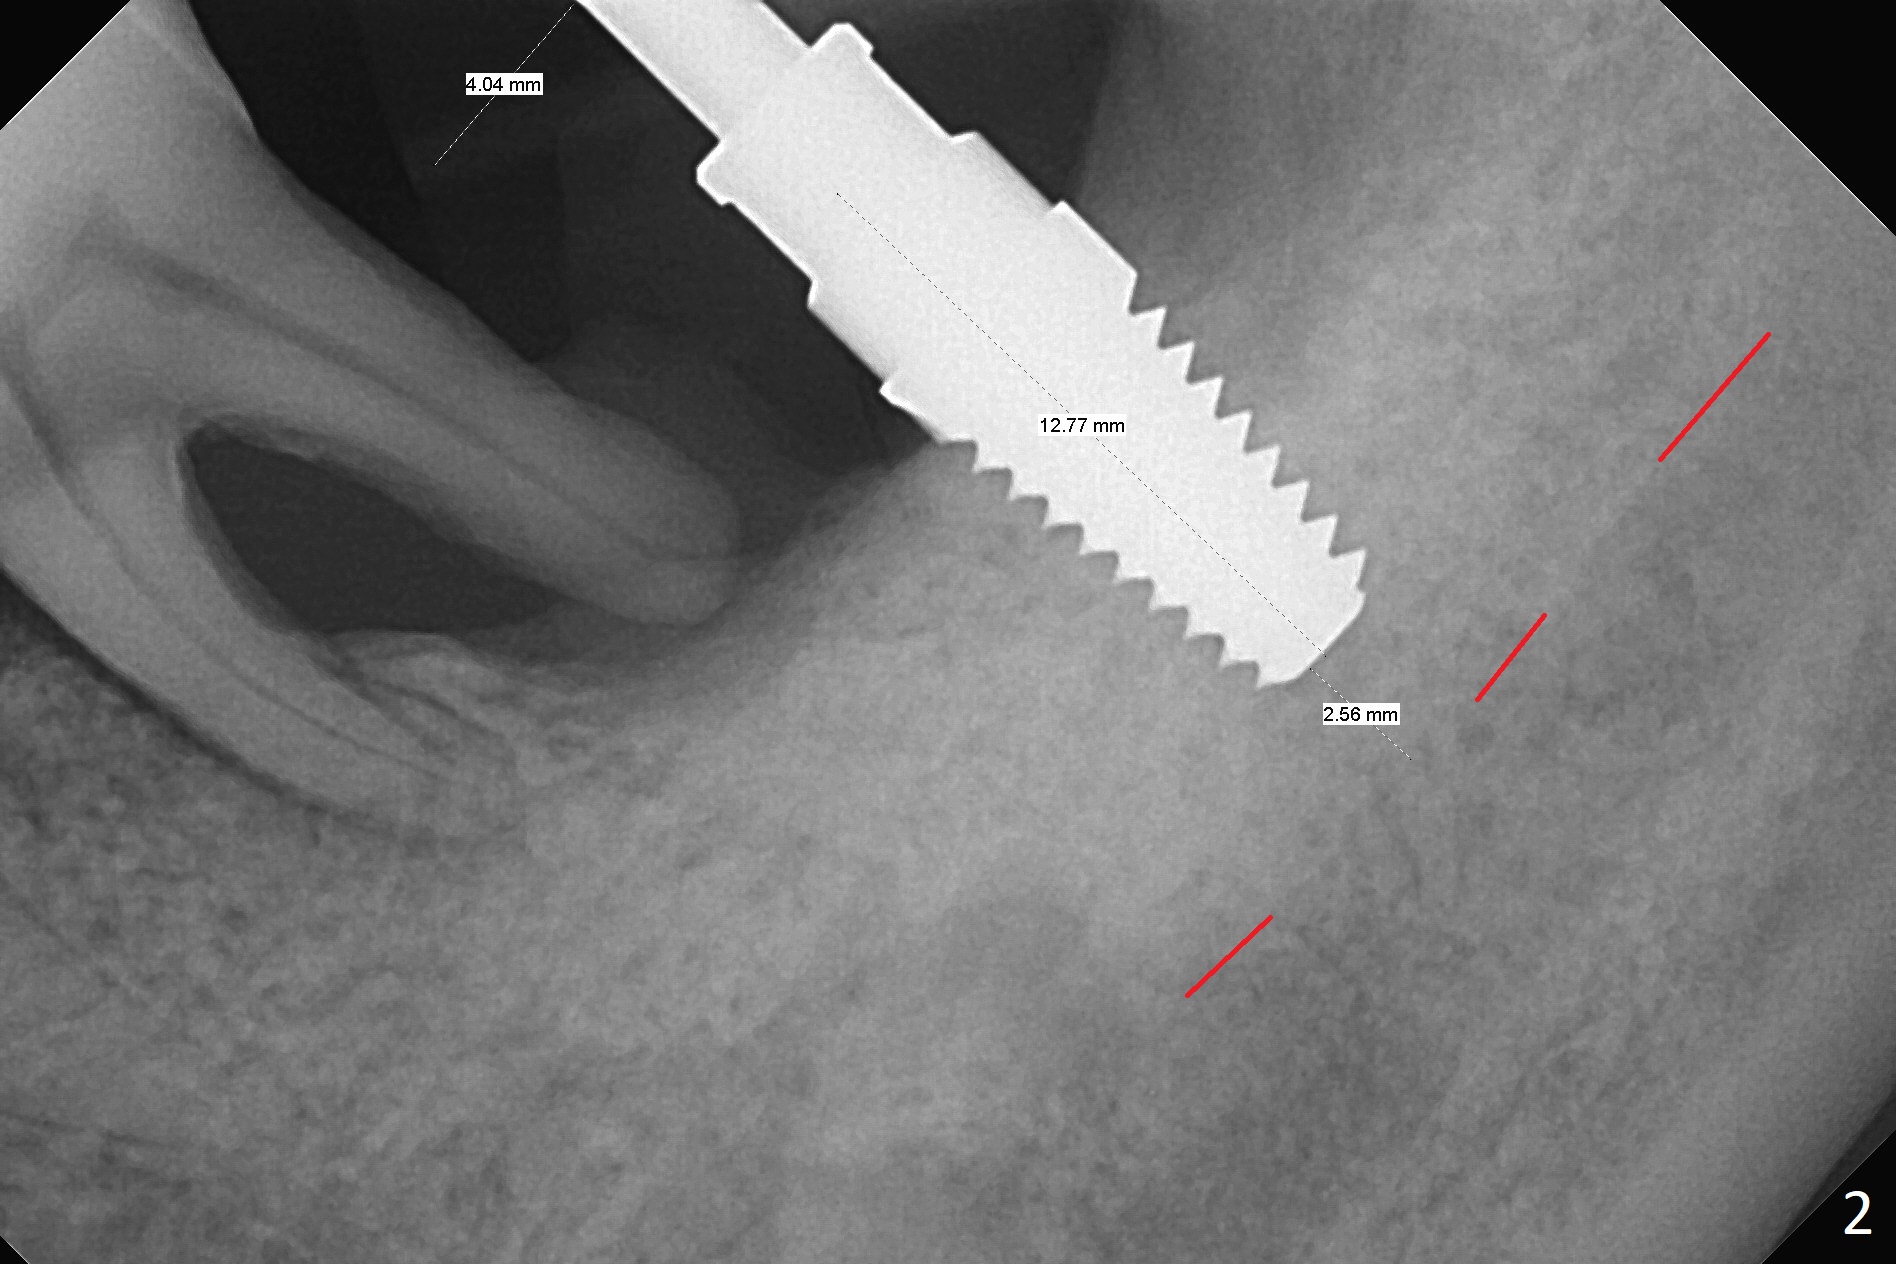

After extraction of the mesioangular tooth #17, initial osteotomy at #18 is 11 mm in depth with sudden empty feel (without pain with infiltration anesthesia); when a parallel pin is inserted, it goes down more than expected (Fig.1). Subsequent osteotomy is strictly controlled at the depth of 11 mm for 2.5 and 3.0 mm reamers. When 3.5 and 4.0 reamers are being used for ~ 9 mm, pain is confined to the coronal portion of the osteotomy, apparently associated with infection from the socket of #17 or from the distal apex of the tooth #19 (scaling & root planing done earlier). After addition of local anesthetic (infiltration), a 5x11 mm tap is inserted (Fig.2). With sufficient clearance from the Inferior Alveolar Canal (Fig.1-3 red dashed line), block anesthesia is administered. A 5x11 mm Tatum implant is placed with >50 Ncm (Fig.3). A 4.5x5 mm abutment is placed to increase retention of periodontal dressing. Impression is taken 4 months postop (Fig.4). The tooth #19 is symptomatic 7 months post #18 cementation.